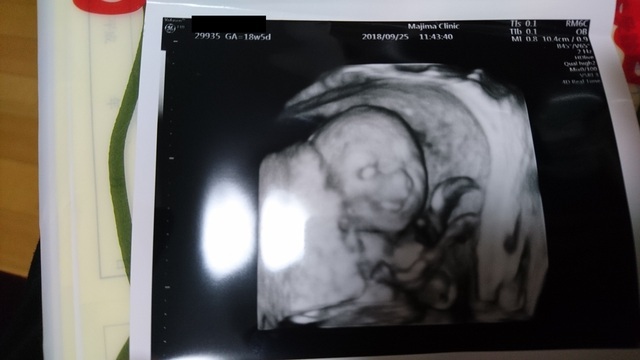

18週1日(18w1d・男の子)|はーちん さん(27歳)

エコー写真撮影時のエピソード:

性別が8割男の子だと分かったときです。毎回楽しみにしているエコー。4週間に1度の検診が楽しみであり不安でもあり毎回ドキドキしています。

1番はっきりと顔が見えたエコー写真で、これ以降下を向いていたり横を向いていたりとなかなかお顔を見せてくれません。なので産まれてくるのがもっと楽しみです!